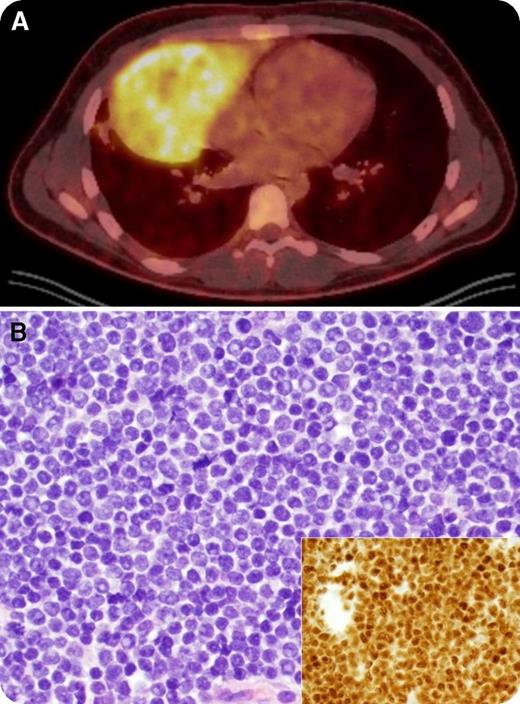

An 18-year-old man presented with a 2-month history of unintentional 23-kg weight loss, night sweats, and left-sided neck swelling. Physical examination revealed left supraclavicular lymphadenopathy. A complete blood count was within normal limits (white blood cells, 6.6 × 109/L) and a peripheral blood smear only identified a rare immature cell. Positron emission tomography showed a 16- × 9-cm hypermetabolic mediastinal mass mirroring the heart in the right hemithorax (panel A, “double-heart” sign) and extending into the neck. Biopsy of the mediastinal mass revealed a diffuse infiltrate of intermediate-sized T lymphoblasts with high nuclear-to-cytoplasmic ratio, fine chromatin, prominent nucleoli, and frequent mitotic figures (panel B; original magnification ×400; main panel, hematoxylin and eosin stain; inset, terminal deoxynucleotidyl transferase stain). The bone marrow was 50% involved, establishing a diagnosis of T-cell acute lymphoblastic leukemia (T-ALL). Cervical lymphadenopathy resolved completely on physical examination within 2 days of starting steroids as a component of AALL1231 and the patient achieved a complete remission after 1 cycle.